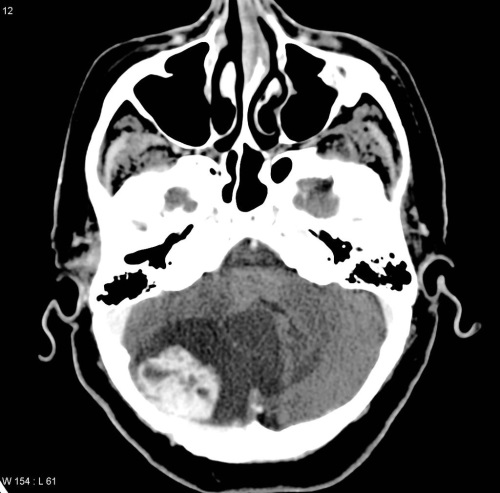

CT scan showing a cerebellar haemangioma in a patient with Von Hippel-Lindau syndrome.